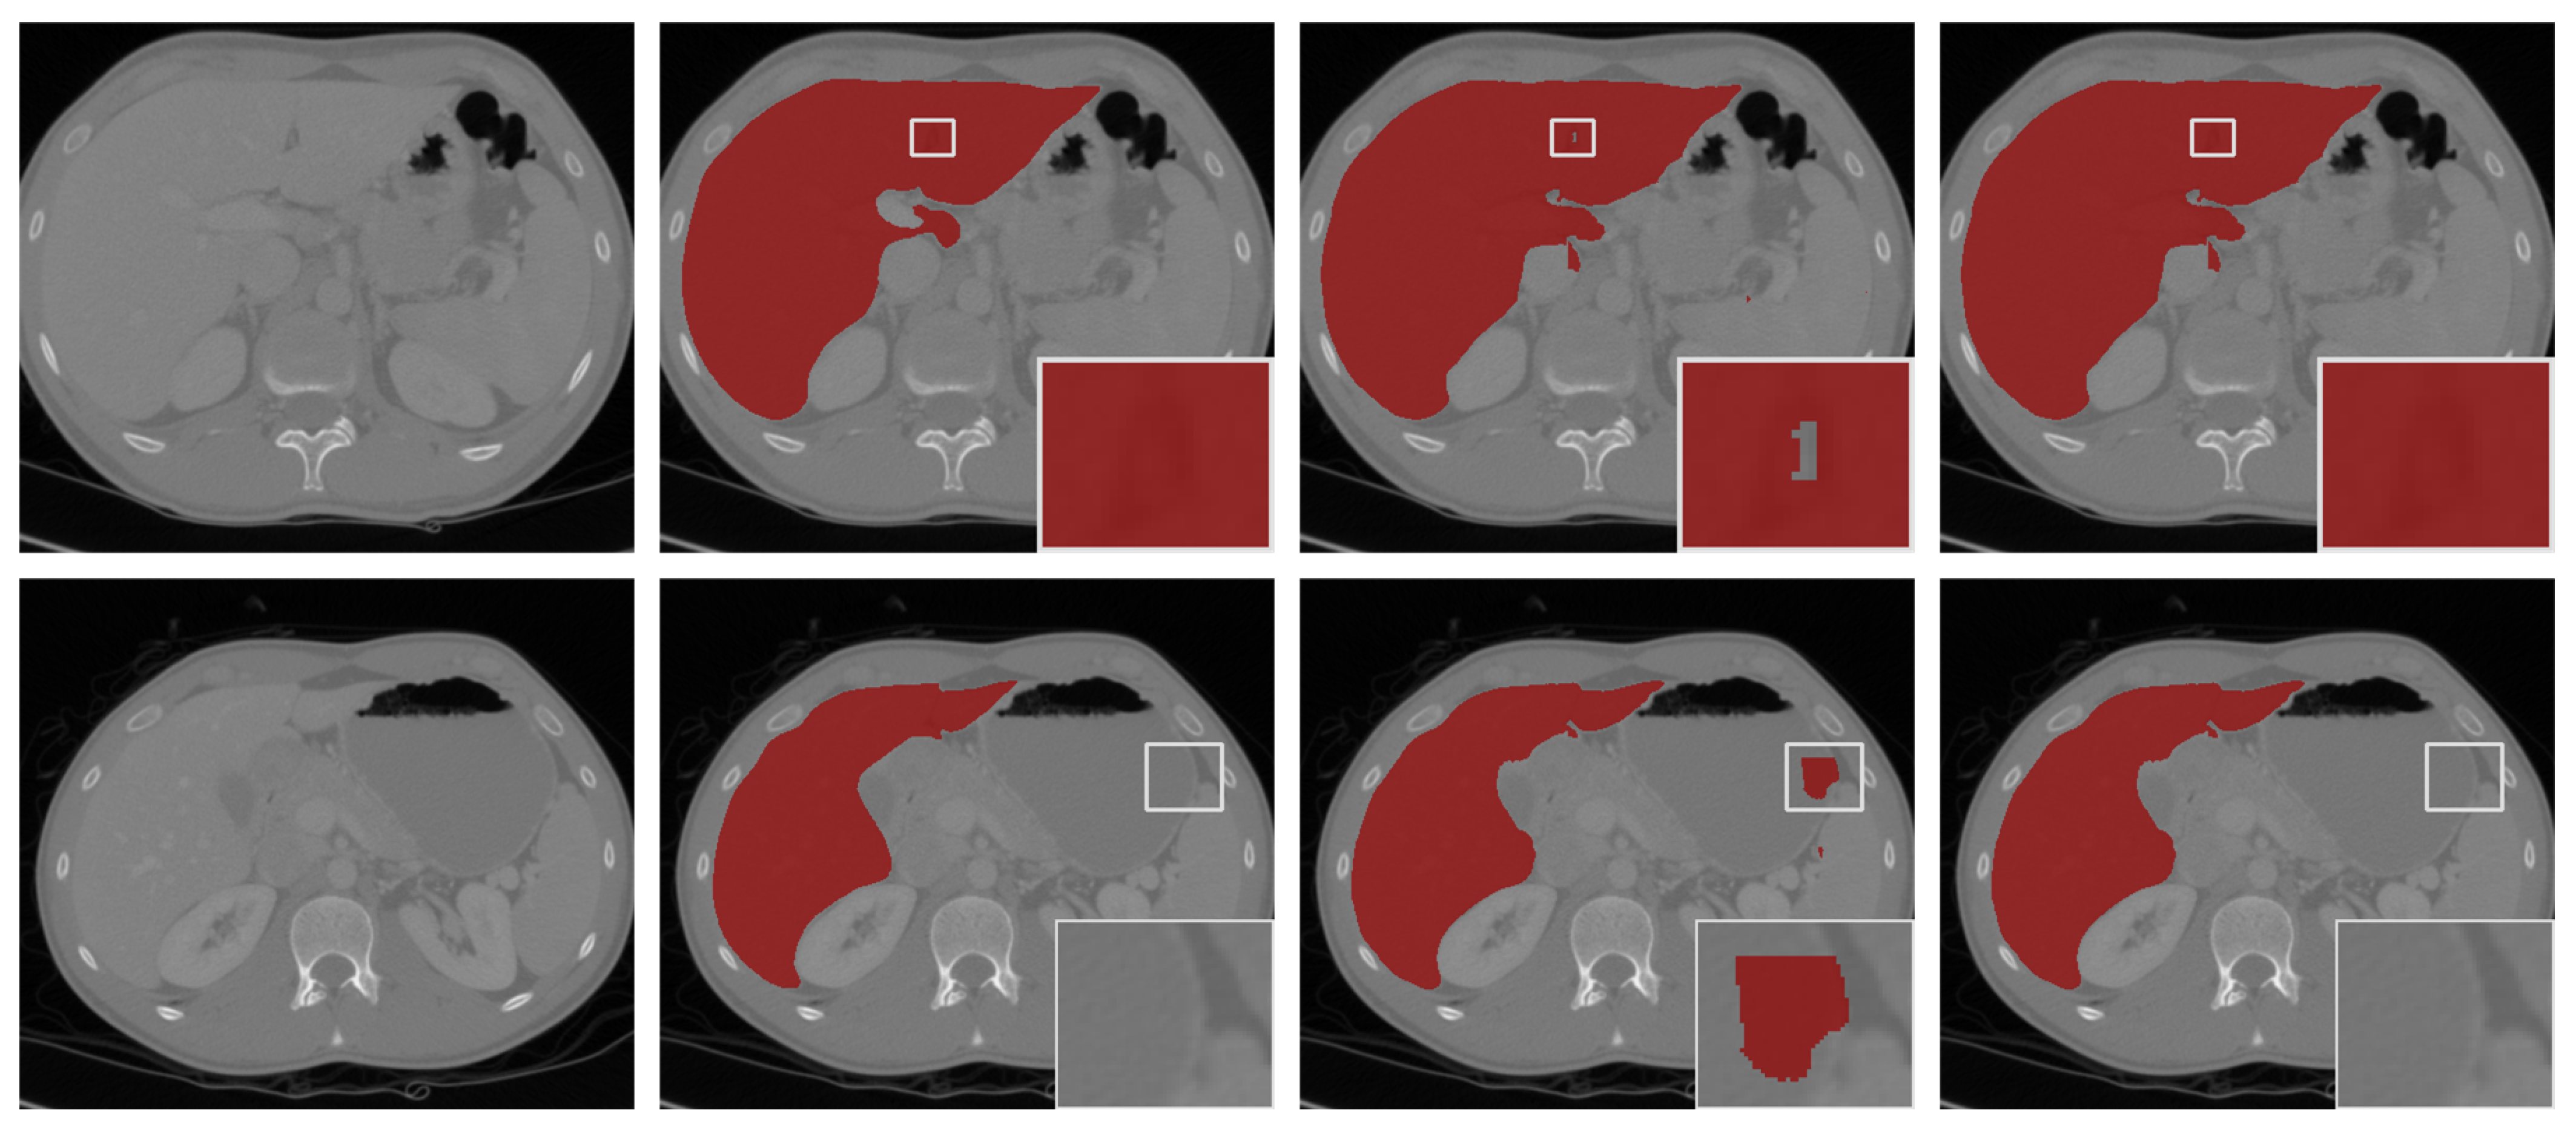

We show visual comparisons before and after post-processing in Figure 6. The results demonstrated that the “hole” (the first row in Figure 6) was effectively filled, and the “island” (the second row in Figure 6) in the background was removed by post-processing. The experiments indicated that our model-driven approach with post-processing was more effective.

Figure 6.

The segmentation results with post-processing. From left to right: the selected scans of the validation set (first column), ground-truths (second column), segmentation results of 3D FAS-UNet without post-processing (third column), and results with post-processing (fourth column).